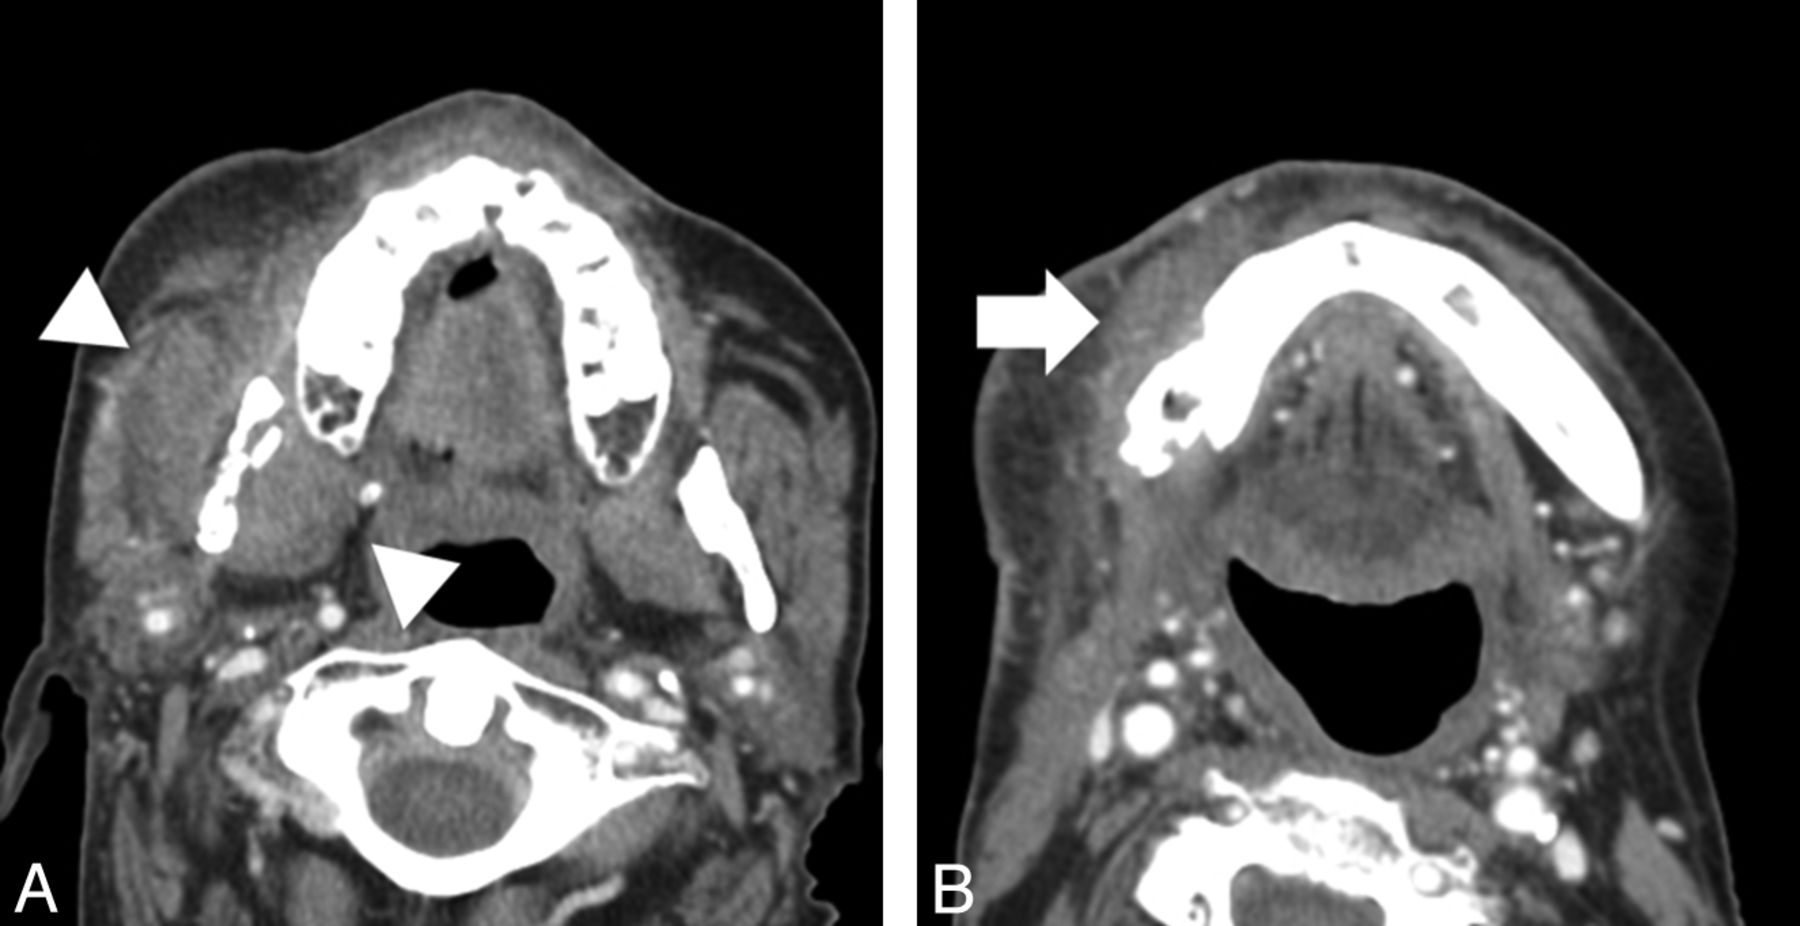

All CT examinations were reviewed retrospectively in random order, separately by 2 Certificate of Added Qualification–certified neuroradiologists (L.A., S.F.), blinded to the clinical findings, the original study interpretation, and the final pathologic diagnosis. Reviewers were asked to comment on the presence or absence of the following imaging findings: 1) a solid measurable mass, 2) a cystic mass, 3) interruption of the cortical margin of the affected bone, 4) fragmentation of the affected bone, 5) loss of trabecula of the affected bone, 6) intraosseous gas in the affected bone, and 7) sclerosis of the affected bone. They were instructed that surrounding inflammatory change (ie, amorphous soft-tissue stranding or infiltration) and muscle or tissue thickening (Fig 1A, -B) did not qualify as a solid mass and that a discrete measurable mass (Fig 2) must be present. They were further asked to measure the size of any solid or cystic mass (Fig 2E, -F), and in those cases in which trabecular loss existed, they were asked to classify the pattern of trabecular loss as either permeative or lucent. They were instructed that a permeative pattern indicated multiple, independent focal lucent lesions, which, in sum, did not account for >75% loss of total bone trabecula (Fig 3A). A lucent pattern was defined as >75% loss of total bone trabecula in the area of abnormality (Fig 2C, -D). Radiologists were also asked to record the area or areas of the mandible affected, with choices being either the right or left mandibular condyle, coronoid process, ramus, angle, or body.

Images from 2 different patients with osseous findings of osteoradionecrosis. A, Axial CT scan (bone algorithm) shows ORN involving the mandibular angle with an adjacent soft-tissue defect. Areas of permeative trabecular loss (white arrow) are evident. B, Axial CT scan (bone algorithm) shows ORN involving the left mandibular body with bony sclerotic changes (white arrow) evident.

Osseous findings on CT can also be extremely helpful in differentiating ORN from tumor recurrence. Multiple prior studies have delineated the classic bony CT findings associated with ORN, namely cortical disruption, trabecular loss, bone fragmentation, bony sclerosis, and the presence of intraosseous gas.1,10,11,13,21 However, we tested the value of these imaging findings for discriminating ORN and tumor recurrence. Traditionally, on the basis of known pathologic findings in ORN, it has been thought that a more permeative pattern of bone loss is seen in ORN as opposed to tumor recurrence. This was thought to be related to the fact that irradiation leads to a relatively hypoxic, hypocellular, and hypovascular substrate with an inconsistent ability to remodel tissue loss secondary to radiation-induced injury22; this, in turn, would lead to relatively less bony loss than would be seen when tissue is being actively destroyed and replaced by tumor. In our patients, the permeative pattern of bone loss, though significantly more common in ORN, was also seen in a significant minority of patients with tumor recurrence. This may be related to our patient population, which is actively surveyed both clinically and with imaging for tumor recurrence. This hypervigilance for tumor recurrence may lead to earlier detection of recurrent tumor, which may show less advanced bony replacement, mimicking the more restrained bone loss seen in ORN. Similarly, significant bone replacement producing a lucent pattern of trabecular loss, though common in tumor recurrence, was also seen in one-fifth of patients with ORN, presumably reflecting more advanced radiation injury or aggressive infection in this subset of patients.

Perhaps the most useful imaging feature in distinguishing ORN from tumor recurrence was the presence of bony sclerosis (Fig 3B). Seen in nearly one-third of patients with ORN, it was not seen in any of our patients with recurrent tumor. This finding may reflect the tendency of squamous cell carcinoma to induce bony destruction rather than sclerosis in contradistinction to the often chronic nature of ORN that may be associated with bony sclerosis.13,23 Thus, while most patients with ORN may not have bony sclerosis, the presence of this finding on imaging should prompt a relatively confident diagnosis of ORN rather than tumor recurrence. Similarly, intraosseous gas, which has been suggested to be pathognomonic of superimposed osteomyelitis,24 was not seen in any of our patients with tumor recurrence. This finding did not reach significance in our study, however, in part due to its overall rarity on imaging for either entity.